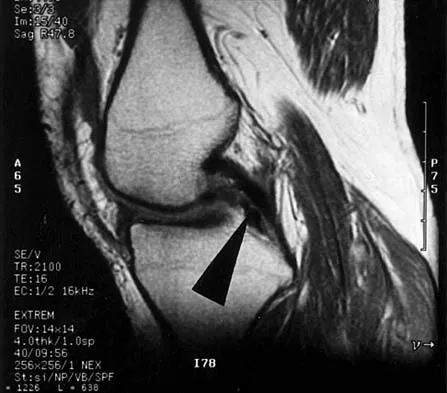

A 73-year-old man stepped off a street curb and felt a crack in his left hip. He is now unable to bear weight. A radiograph is shown in Figure 54a. Biopsy specimens are shown in Figures 54b and 54c. What is the most likely diagnosis?

Explanation